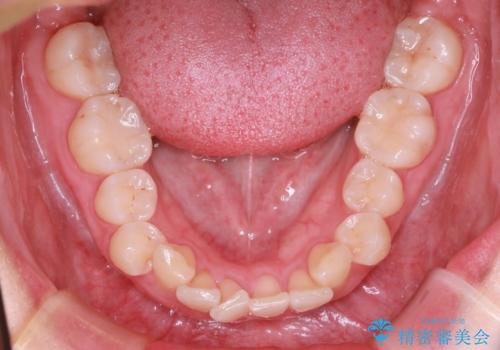

- 前歯の捻れと口元の突出を主訴に来院されました。

インビザラインを用いて上顎の遠心移動を行い、前歯を下げながら凸凹を綺麗に治すことができました。